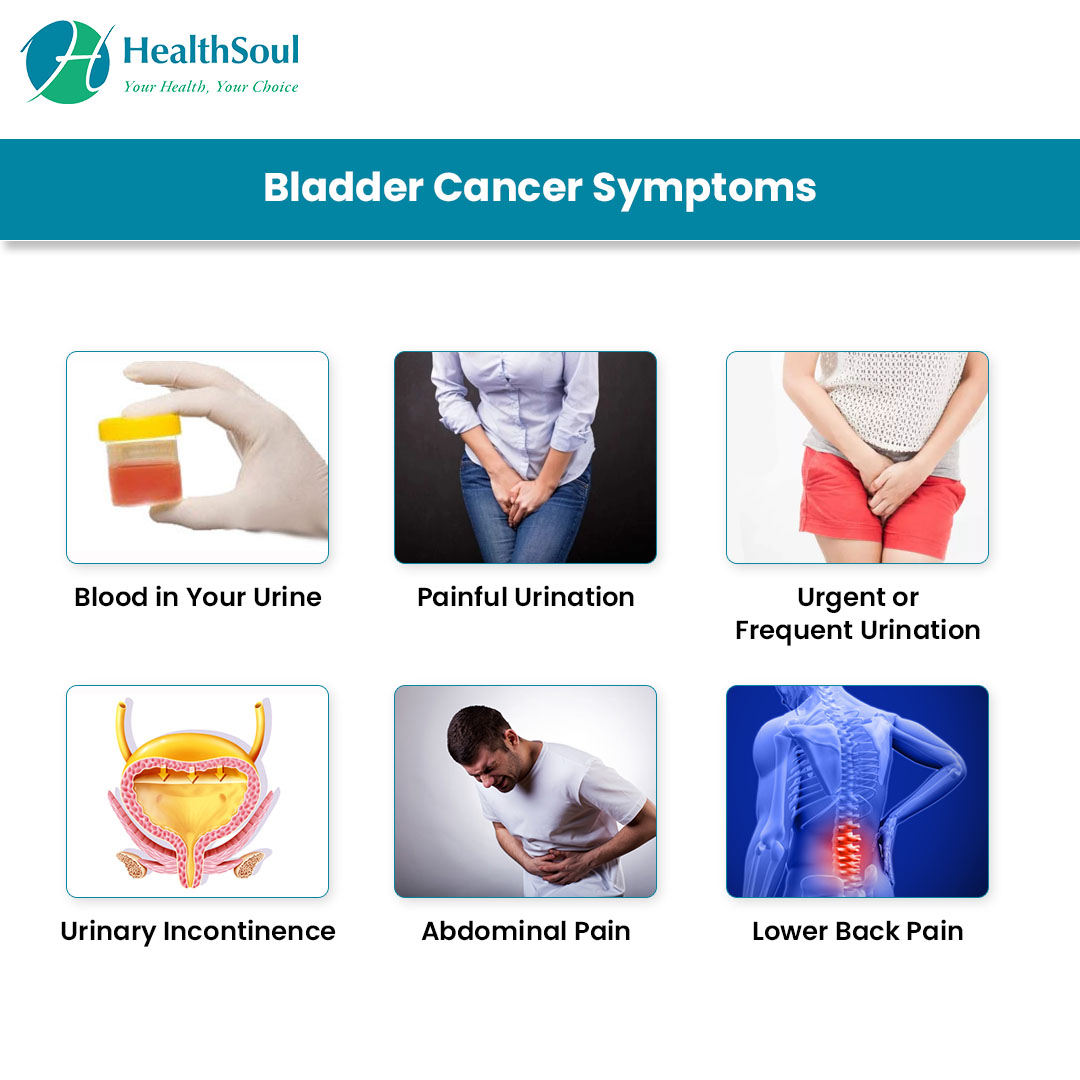

what is the most common sign of bladder cancer Updated

what are the symptoms of bladder cancer in a male Updated

Bladder Cancer: Symptoms and Treatment – Healthsoul

Urinary Bladder Tumour Surgery is done for these SYMPTOMS – Cancerclinix

What Are The Signs Of Bladder Cancer In Males : How We Diagnose Bladder …

What Are The Signs Of Bladder Cancer In Females / Bladder cancer and …

Bladder Cancer. Signs, Symptoms and Treatment of Bladder Cancer